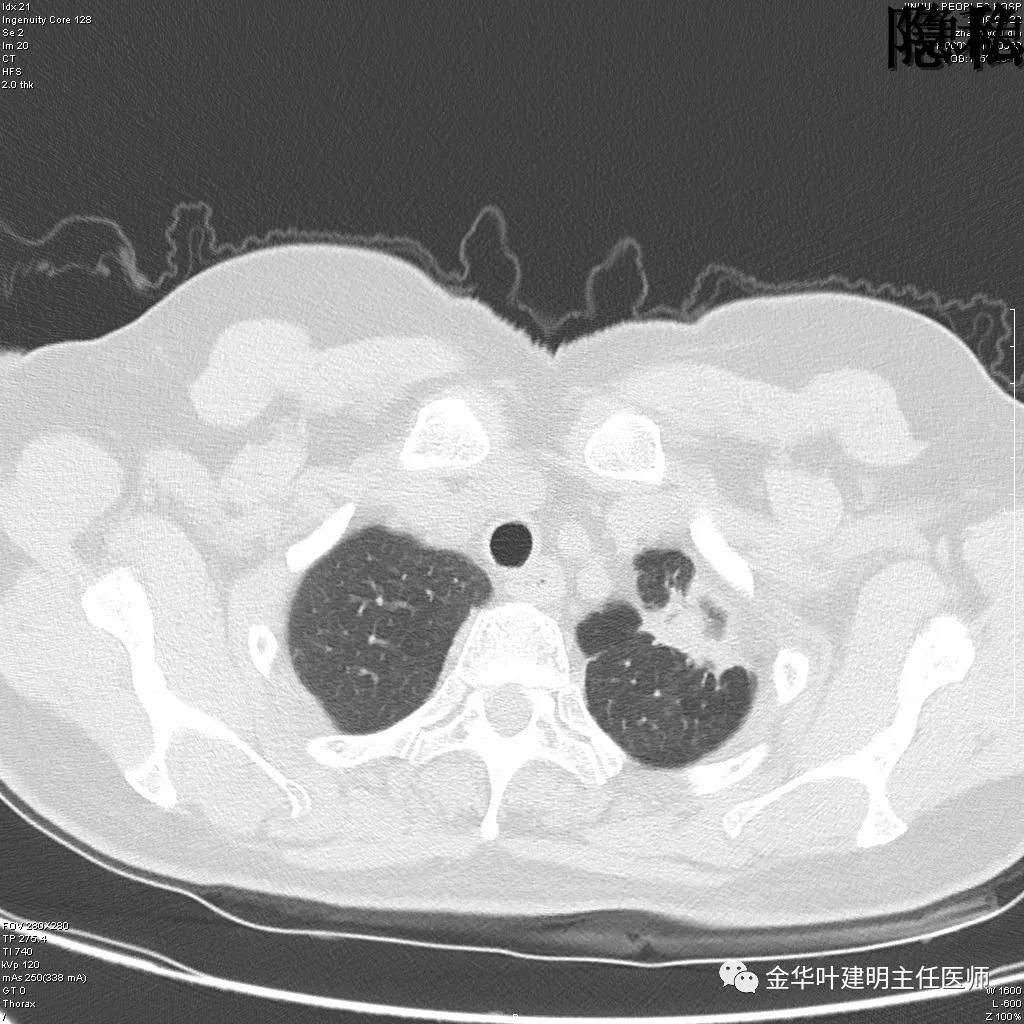

(病例资料2019年)金华的章某,今年60岁,前段时间因为咳嗽,到市区某三甲医院检查,发现她的左肺上叶与左肺下叶都有占位性病变。由于章某有亲戚在我们医院工作,所以在亲戚的指引下,让她来找我。我们予以适当的抗炎治疗,然后复发CT,发现病灶没有任何变化。其中平扫的片子如下:

可见左肺上叶有一占位,是空腔性的,其内有实性密度填充,是比较典型的肺曲菌病的表现,但病灶有点大,长径大于3-4厘米许。